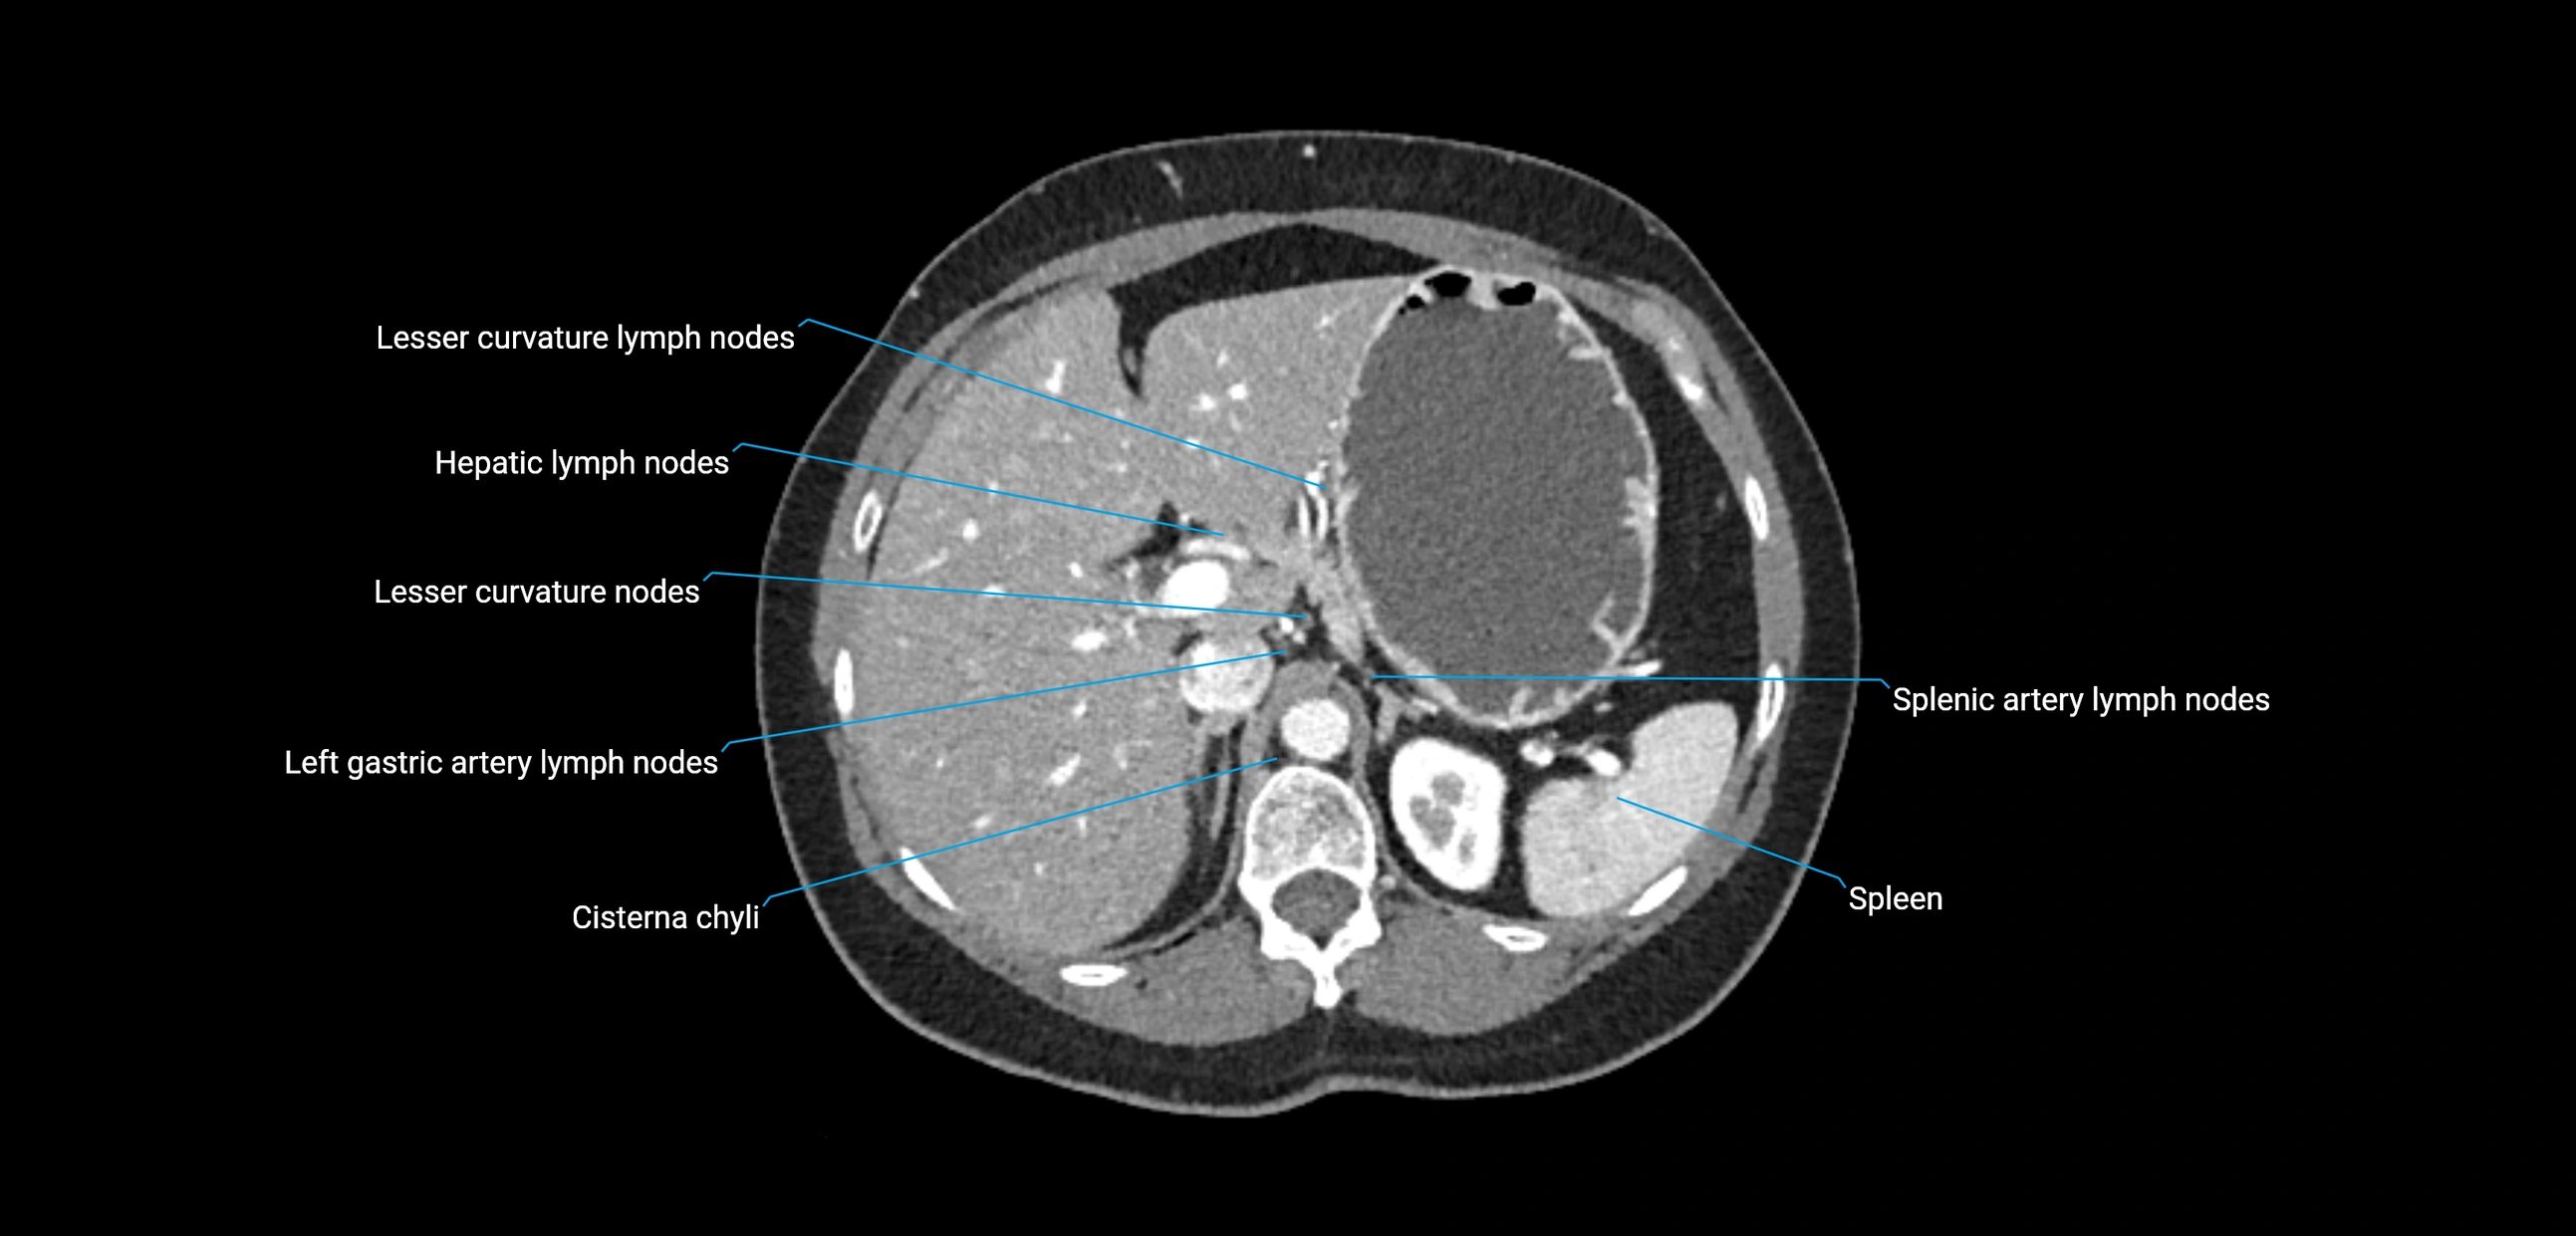

CT image

image